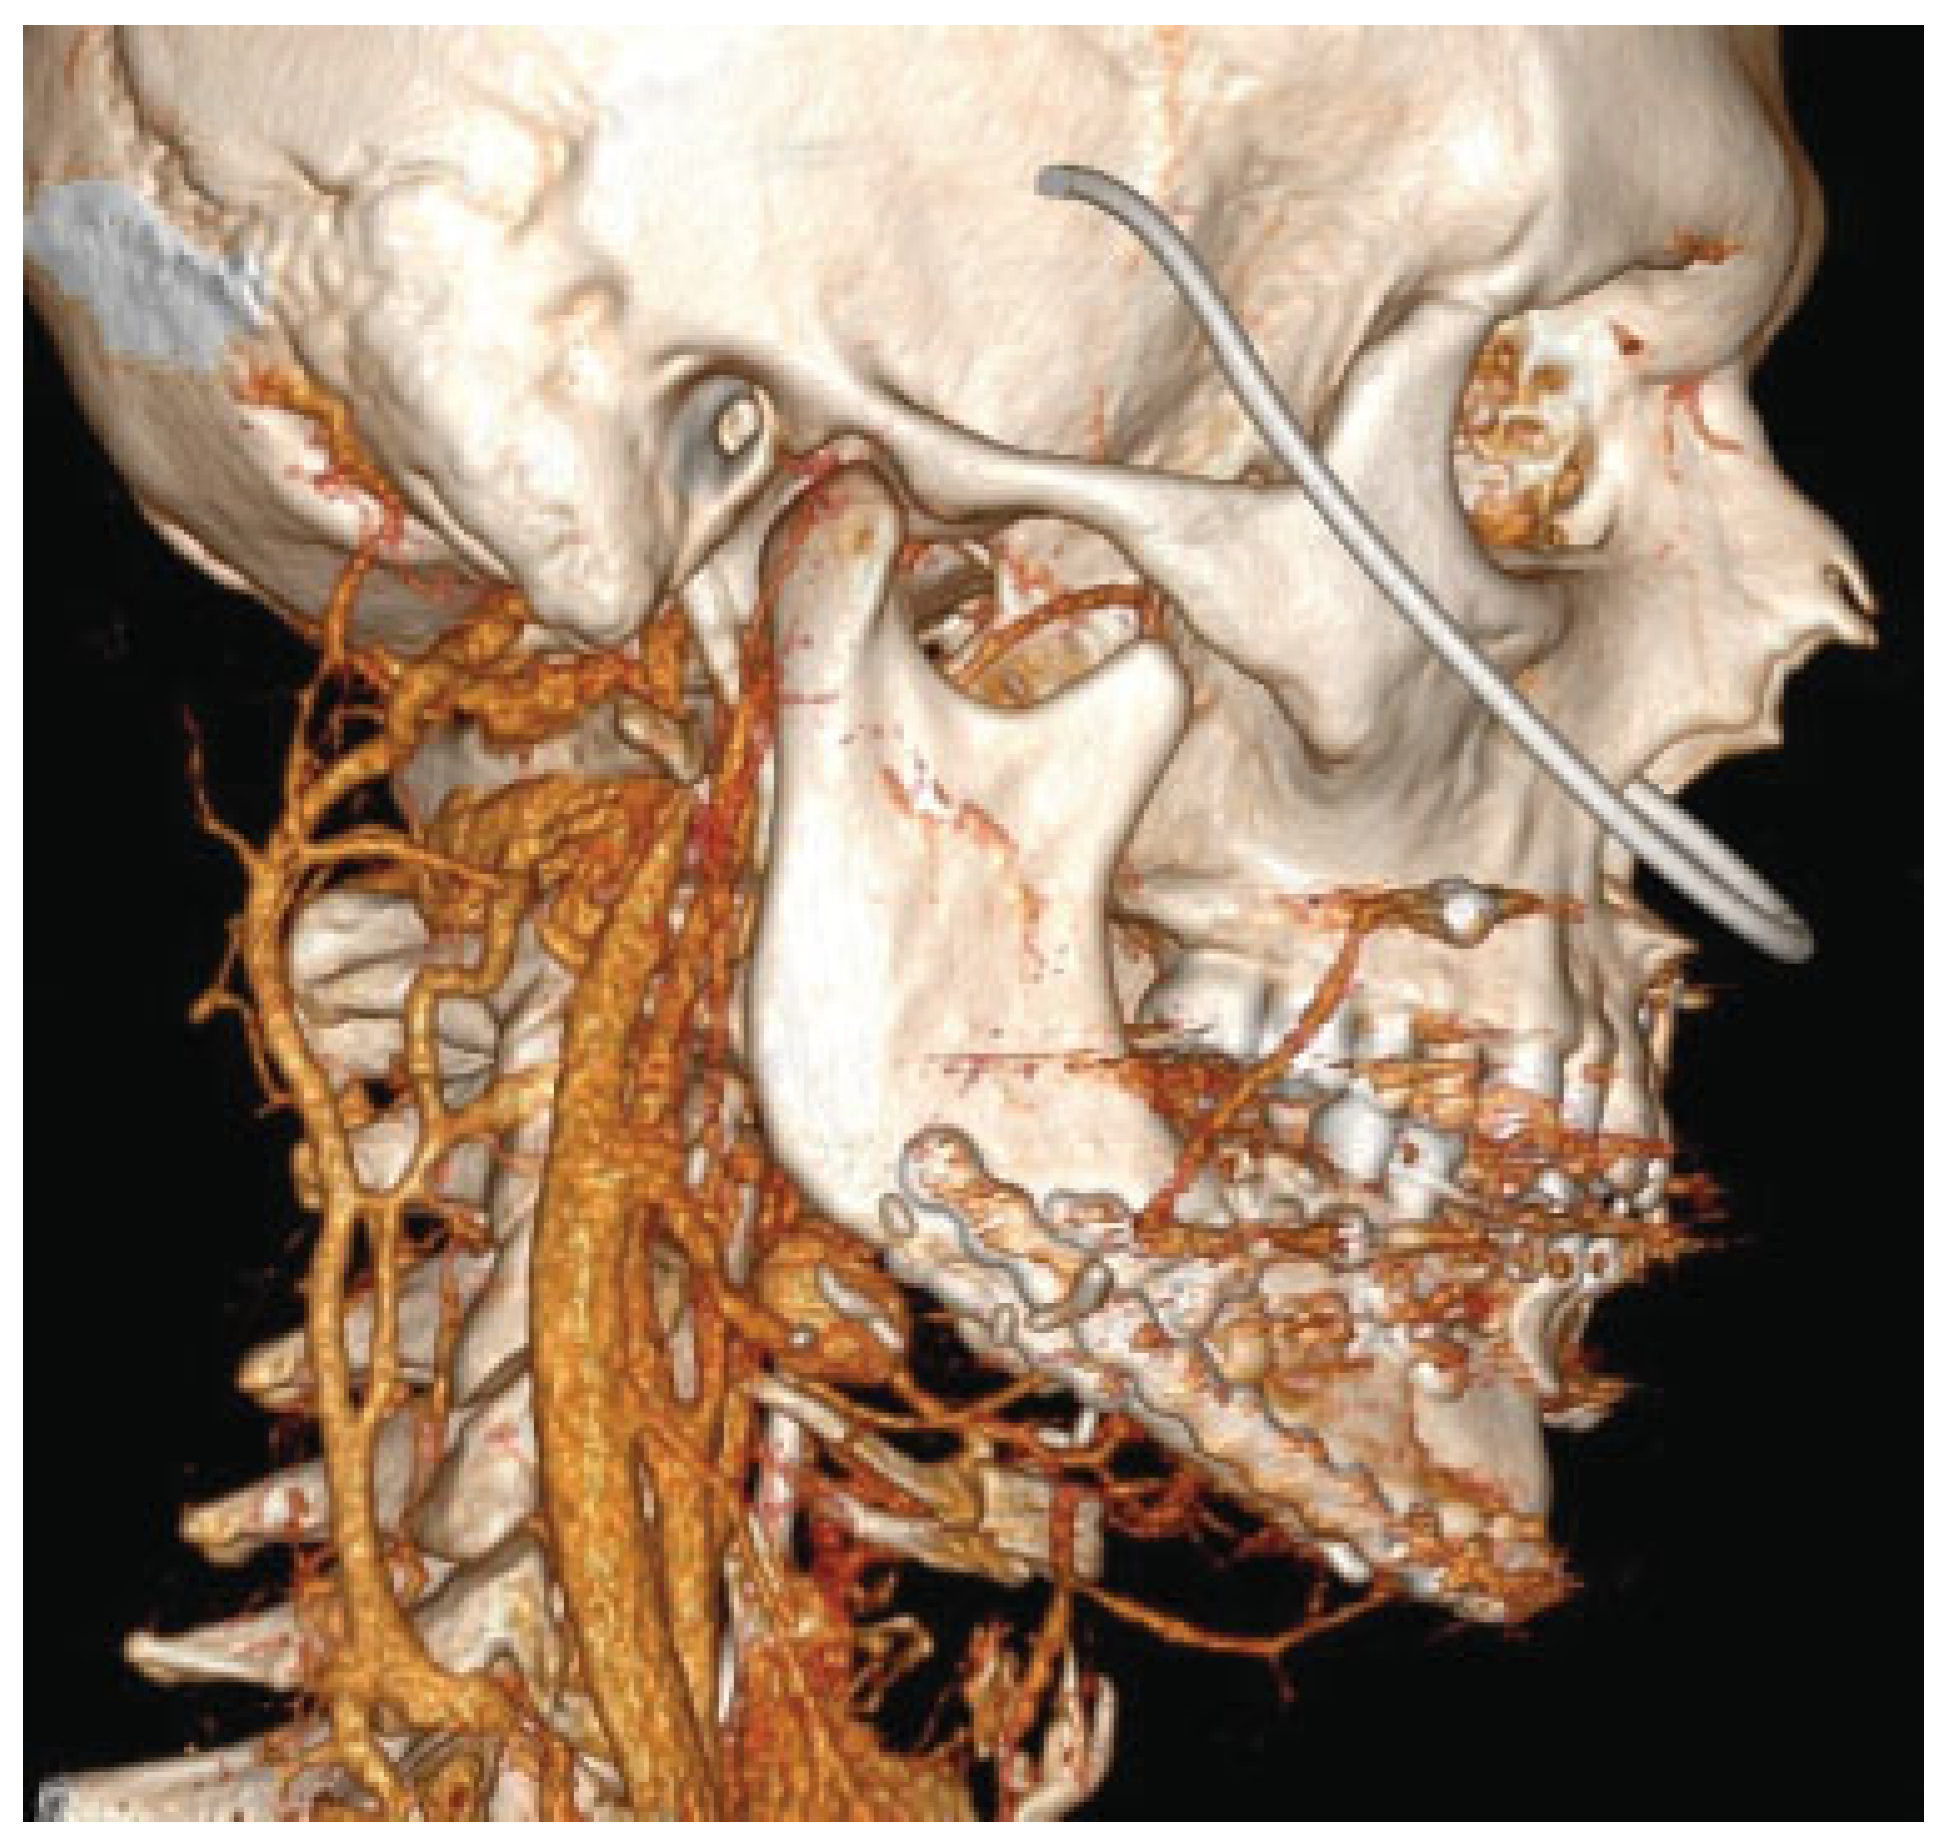

The immediate postoperative course was uneventful, until unprovoked massive intraoral bleeding on postoperative day 14, required an urgent return to the operating room. After initial control of bleeding, the patient underwent intraoperative angiography that diagnosed a 25-mm pseudoaneurysm arising 10 mm distal to the origin of the right lingual artery (

Figure 2), which was superselectively embolized with coils by the interventional radiologist (

Figure 3). The patient was stabilized and was discharged from hospital 3 weeks later (